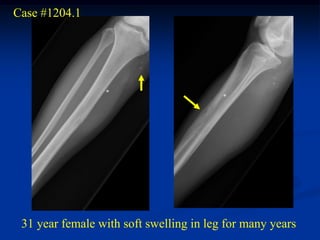

Case #1204.1

31 year female with soft swelling in leg for many years

Axial CT

Cor Ct

Cor T-2   Sag Gad   Sag Gad

Axial Gad   Axial Gad